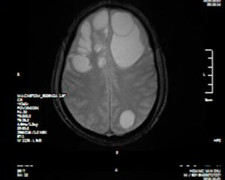

Não người đàn ông tổn thương sau nhiều năm có thói quen ăn tiết canh, thịt tái.

Sau cơn co giật, méo miệng, anh T đi khám và phát hiện sán làm tổ trong não.

Đau đầu ngày càng tăng về cường độ, người đàn ông đi khám tâm thần, uống thuốc nhưng không khỏi, hóa ra anh bị sán làm tổ trong não.

Ổ sán khổng lồ cư trú trong não khiến người đàn ông ở Phú Thọ mất dần trí nhớ, phù não diện rộng, phải phẫu thuật khẩn cấp.